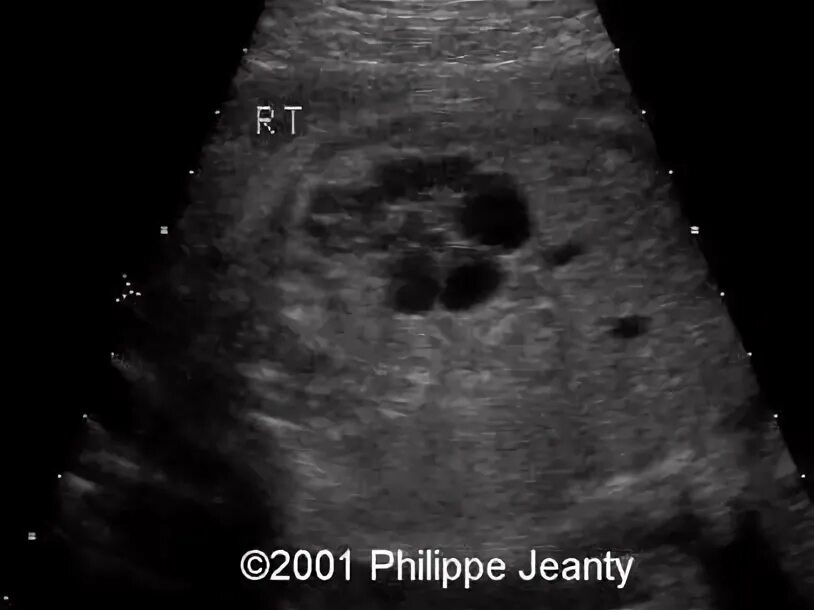

Мультикистозная почек плода